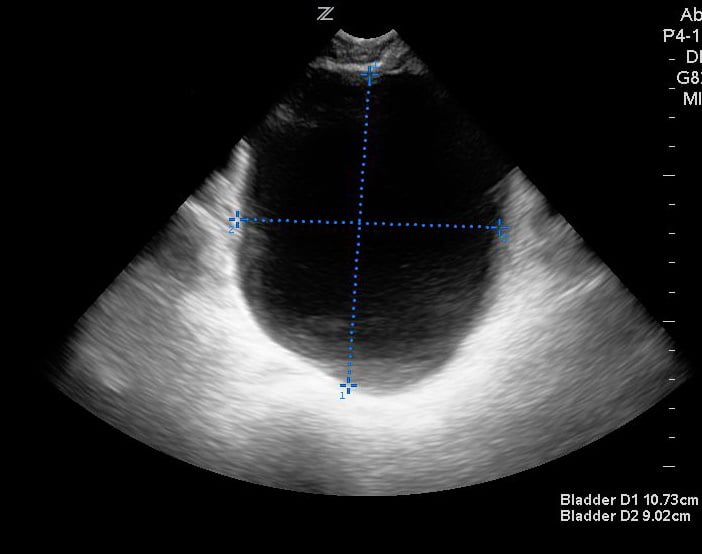

- For measuring bladder volume, use the US volume measurement feature or the formula 0.52 × Depth × Width × Height.

- In the transverse view, find the largest bladder size and measure both the vertical and horizontal length of the bladder image from inner wall to inner wall. This corresponds to the bladder depth and width, respectively.

- In the sagittal plane, measure the maximum horizontal length of the bladder image from inner wall to inner wall. This corresponds to the bladder height.

- Figures 3 and 4. Measurement of bladder volume in the transverse (Figure 3) and sagittal (Figure 4) views